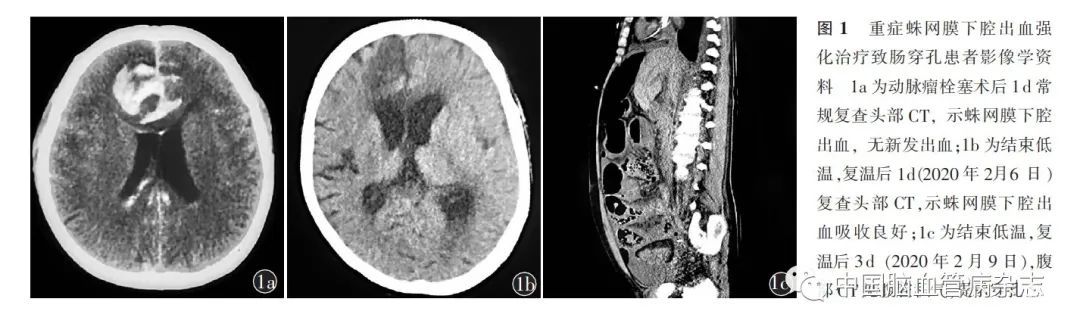

女,48 岁,主因“突发头痛伴恶心呕吐1 d”于2020 年1 月20 日急诊入住首都医科大学宣武医院神经外科。入院前1 d,患者在家突发头痛,伴恶心呕吐,当地医院头部CT 显示蛛网膜下腔出血,行全脑DSA 诊断为颅内动脉瘤,为求进一步治疗转至我院。患者既往系统性红斑狼疮病史10 年,长期口服泼尼松5 mg/ d。入院体格检查:嗜睡,格拉斯哥昏迷量表评分12 分,四肢肌力Ⅴ级,双侧病理征阴性。入院后急诊行全脑DSA 检查,可见前交通动脉动脉瘤,遂行动脉瘤栓塞术。术后即刻造影未见动脉瘤显影,手术过程顺利。术后1 d,常规复查头部CT,示蛛网膜下腔出血量大,未见新发出血(图1a)。患者颅内压波动于20~30 mmHg,行脑室外引流术,释放脑脊液后患者颅内压降至15 mmHg,并同时给予镇痛、镇静及全量甘露醇脱水治疗。栓塞术后2 d,患者出现高热,体温最高达39. 5 ℃ (膀胱温度)。为控制高热,降低颅内压,改善神经功能损伤,遂采用包裹式冰毯机(Allon2001 降温机器,MTRE 公司,以色列)降温,并结合冬眠合剂等镇痛、镇静药物行低温治疗,将膀胱温度控制在35 ℃左右。降温期间,使用瑞芬太尼1. 5 μg/ (kg·h)镇痛,丙泊酚0. 8 mg/ (kg·h)、异丙嗪+ 氯丙嗪+ 杜冷丁各2 mg/ (kg·24h)镇静治疗。维持患者颅内压力在10 ~15mmHg。低温治疗10 d 后,患者颅内压力稳定在15 mmHg 以内。于2020 年2 月4 日开始程序复温,复温过程中调整冰毯机温度设定目标,温度升高1℃ /24 h,经48 h,复温至36. 5℃,并逐渐减少镇痛、镇静药物剂量至停止,复温期间应用氢化可的松替代治疗。复温开始1 d(2020 年2 月6 日),复查头部CT,示蛛网膜下腔出血吸收良好(图1b)。患者颅内压力稳定,间断行腰椎穿刺序贯治疗。结束复温后3 d (2020 年2 月9 日),患者出现高热、腹胀、未排便,体格检查示昏迷,格拉斯哥昏迷量表评分6 分,肌紧张,压痛、反跳痛明显,肠鸣音消失。急行腹部CT 检查,示腹腔积气、积液(图1c),提示肠穿孔。行床旁腹腔穿刺术,可见浑浊黄褐色液体。患者持续高热(膀胱温39~40 ℃),心率快、血压低,泵入去甲肾上腺素以维持血压。患者生命体征进一步恶化,考虑为严重脓毒血症、休克。患者家属拒绝行剖腹探查术,最终死亡。